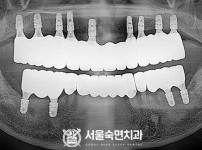

상악동거상술, 뼈이식 / 숙면임플란트 14개 - 네오임플란트 (이*현님)

해당 게시물은 의료법 제56조에 의거하여 로그인 후 열람이 가능합니다.

구분 임플란트